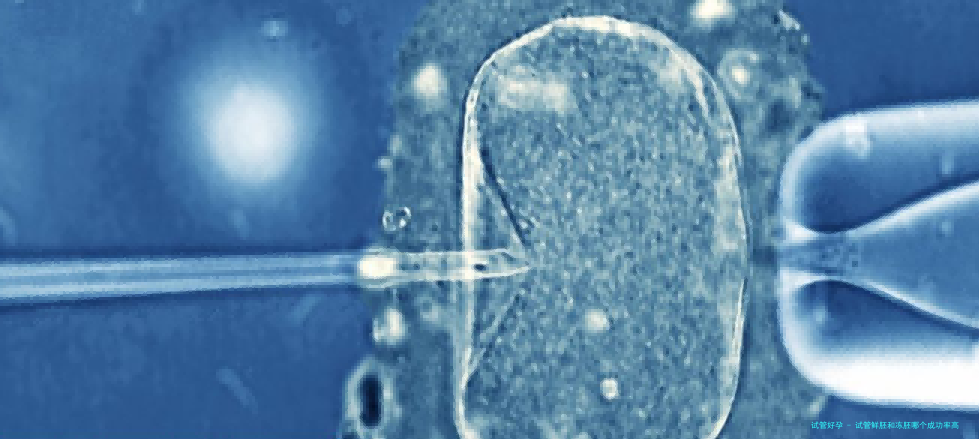

在试管婴儿助孕期间,许许多多女性十分困难等到胚胎移植阶段,却被医生告知不适合进行鲜胚移植,只能等调养好后再进行冻胚移植。她们的内心便开始发生疑虑:“鲜胚移植不用经历胚胎冷冻和复苏等环节,更具有活力、更吻合自然法则,想当然的就更轻易成功。如此,冻胚移植是不是没有鲜胚移植好?鲜胚移植和冻胚移植哪一个成功率更高些?针对这一些问题,下面小编就来帮大家解除这个疑虑。

鲜胚移植是指试管取卵后3天内,卵子和精子在体外受精形成早期胚胎,在新鲜的周期直接进行胚胎移植,其好处就是激起试管胚胎的生长发育潜力、缩小试管婴儿的治疗时间,具体分析如下: